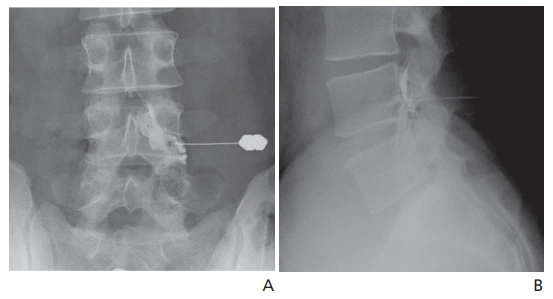

2. 선택적 신경근 차단술(Selective nerve root block)

출처) Selective Nerve Root Block. Bone and Spine(PAIN MANAGEMENT, PROCEDURES)

위 사진처럼 선택적으로 "왼쪽 요추 3번 신경(Left L3 nerve root)" 만을 타깃으로 하여 약물을 주입하는 것을 선택적 신경근 차단술이라 한다.